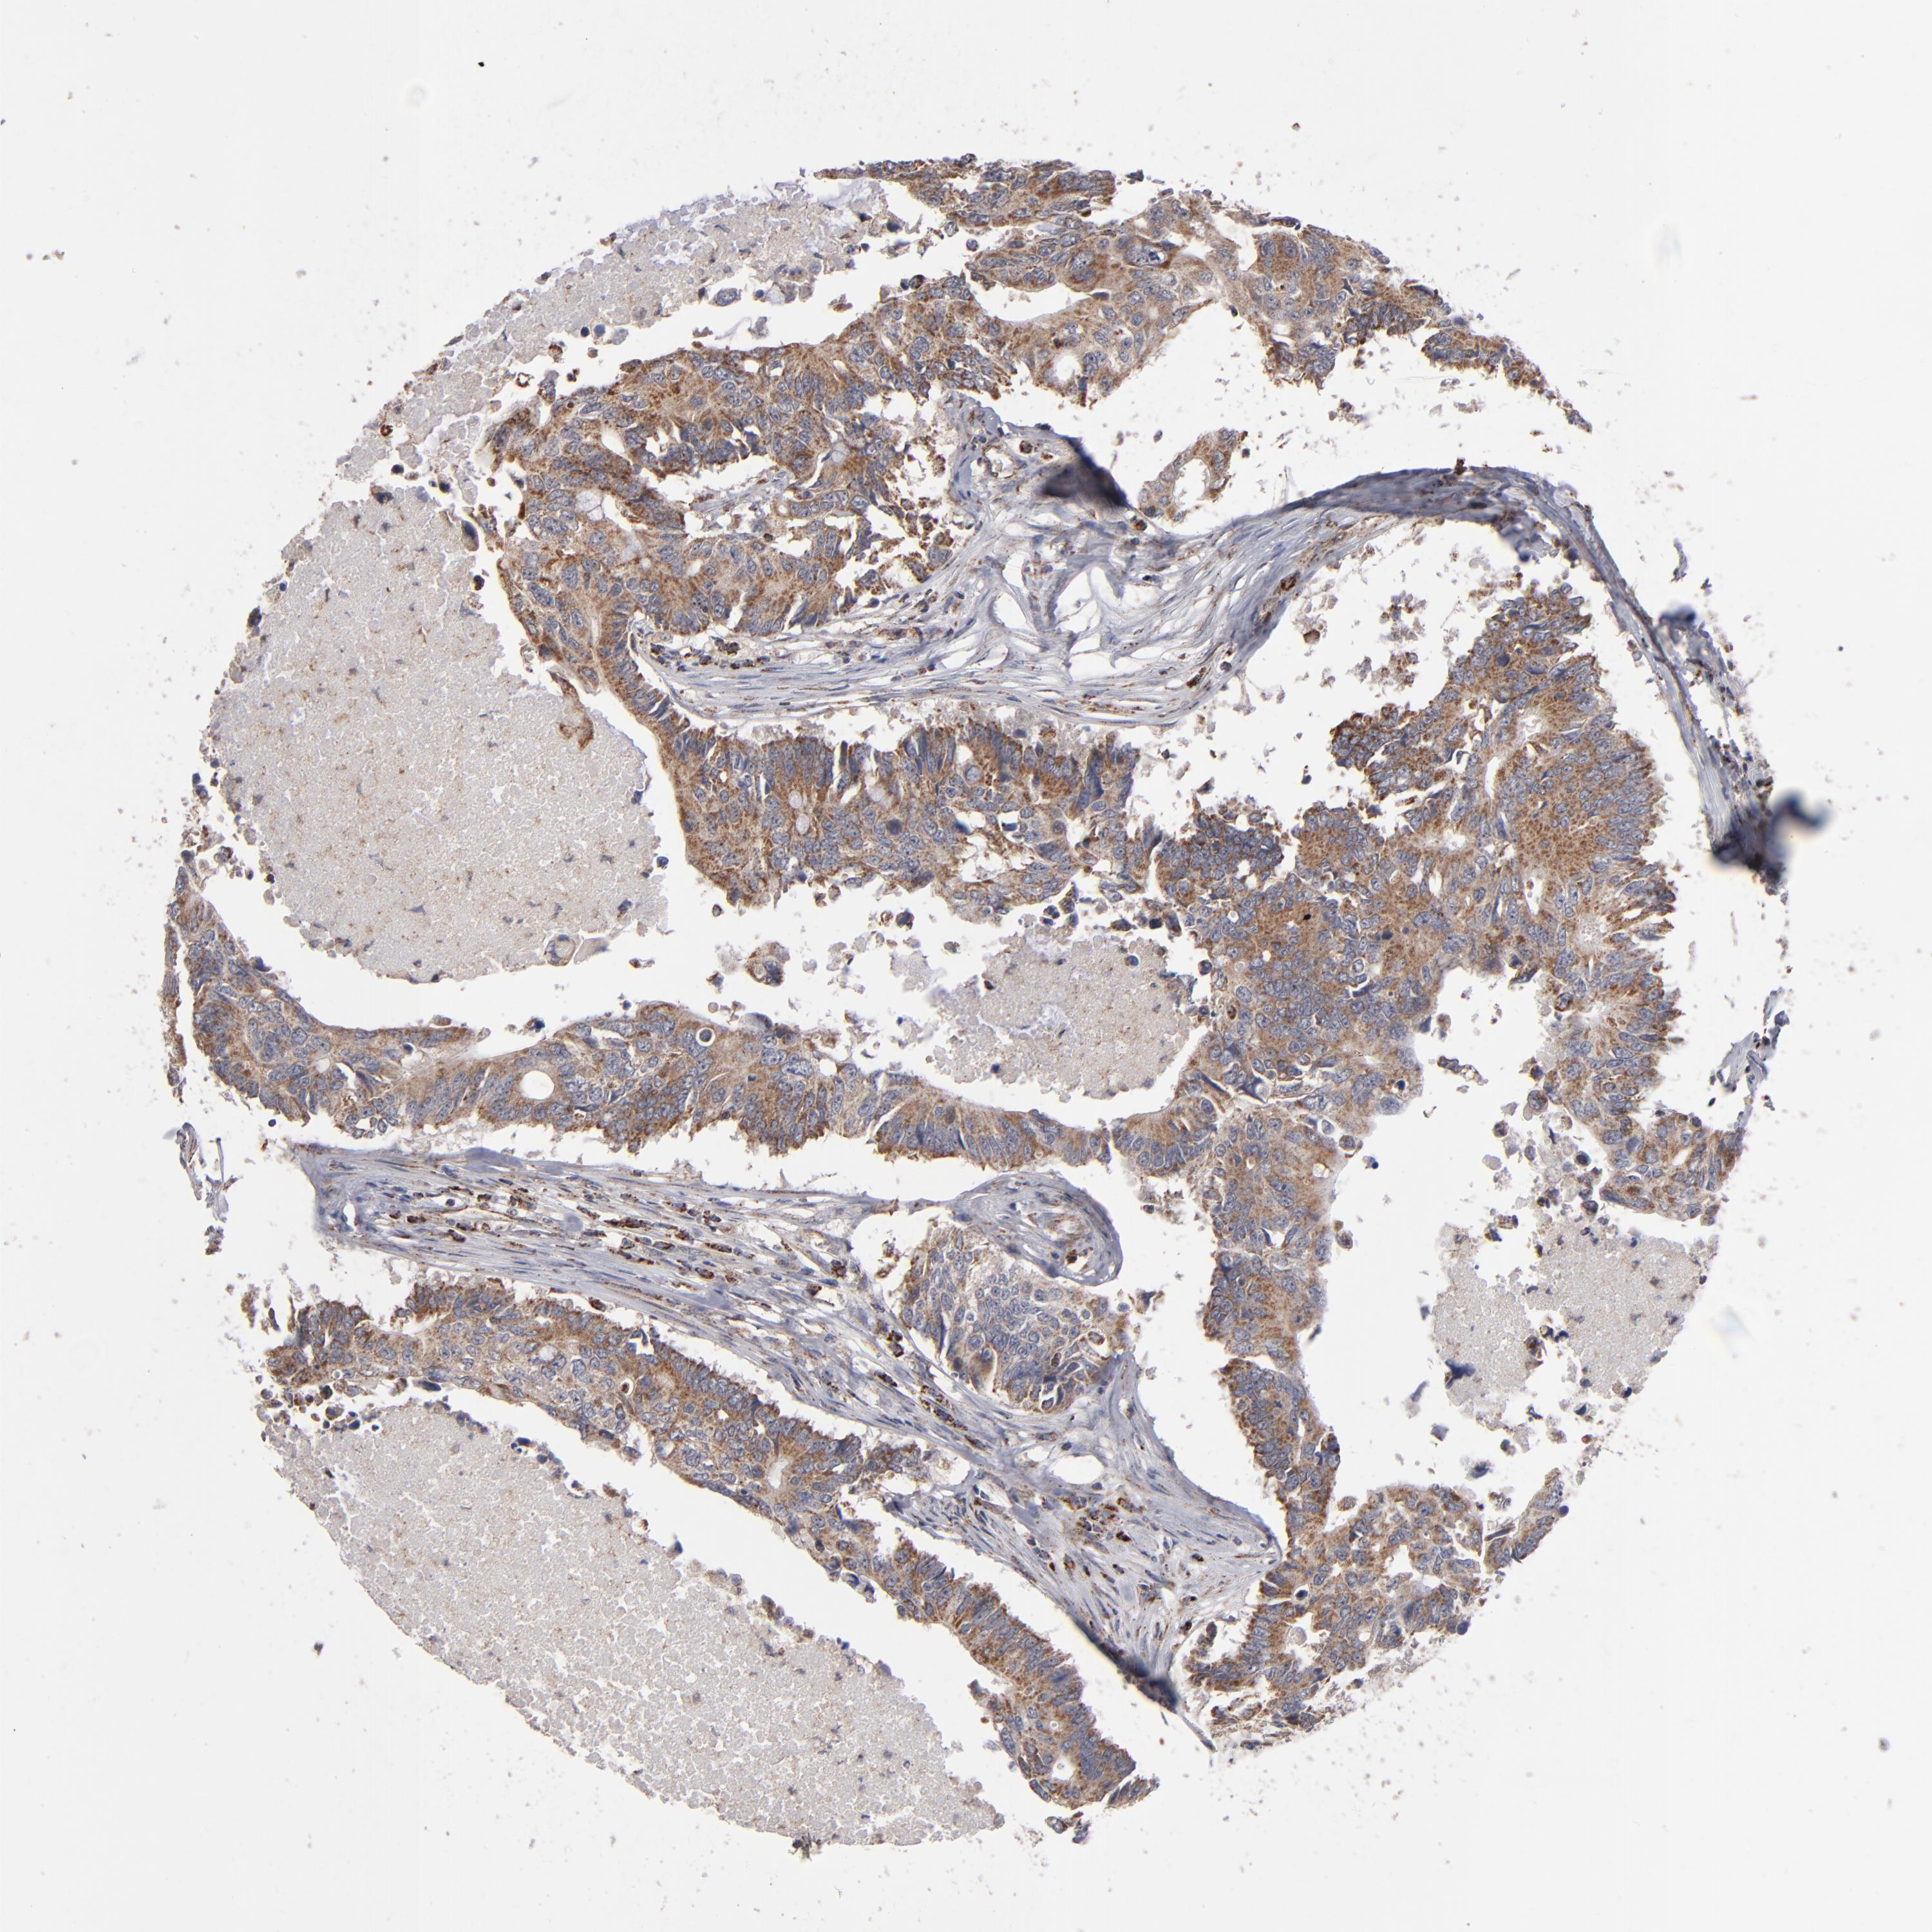

CANCER COLORECTAL CANCER Show tissue menu

Colorectal cancer

Human cancer

Colon adenocarcinoma

Rectum adenocarcinoma